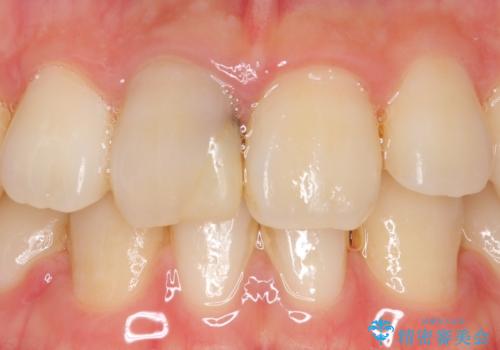

- 右上1番目の前歯の変色が気になるといらっしゃった方の症例です。

再根管治療後、オールセラミッククラウンによる補綴を行いました。

今回用いたオールセラミッククラウンはジルコニアフレームという白い素材の上にセラミックを盛っているため、審美性が非常に高いのが特徴です。

また、ジルコニアは人工ダイヤモンドの材料にも使われているほど高い強度を持っており、そのためオールセラミッククラウンは審美性だけでなく、奥歯やブリッジの補綴も可能とするクラウンです。